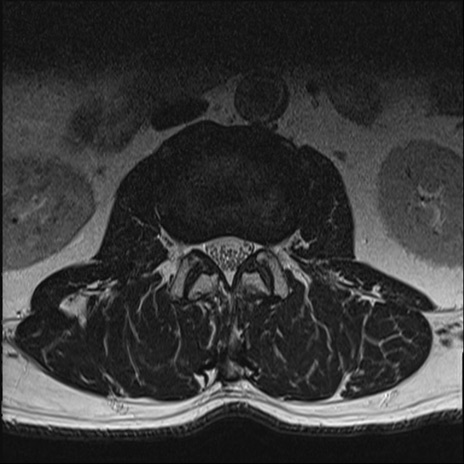

【整形】TIPS症例2 腰椎MRI T2WI(横断像)

【症例】70歳代男性

【主訴】左下肢痛

【現病歴】2週間前くらいから腰痛、左下肢痛あり。左臀部から大腿、下腿外側のしびれが常時ある。歩行とともに同部位の痛みあり。

【身体所見】Lasegue70-/60+、Bragard-/±、PTR ±/±、ATR -/-、IP 5/5、TA 5/4、TS 5/5、EHL 右第1足趾なし/3、FHL 5/5、hypersthesia(-)、足背動脈触知良好

異常所見と診断は?